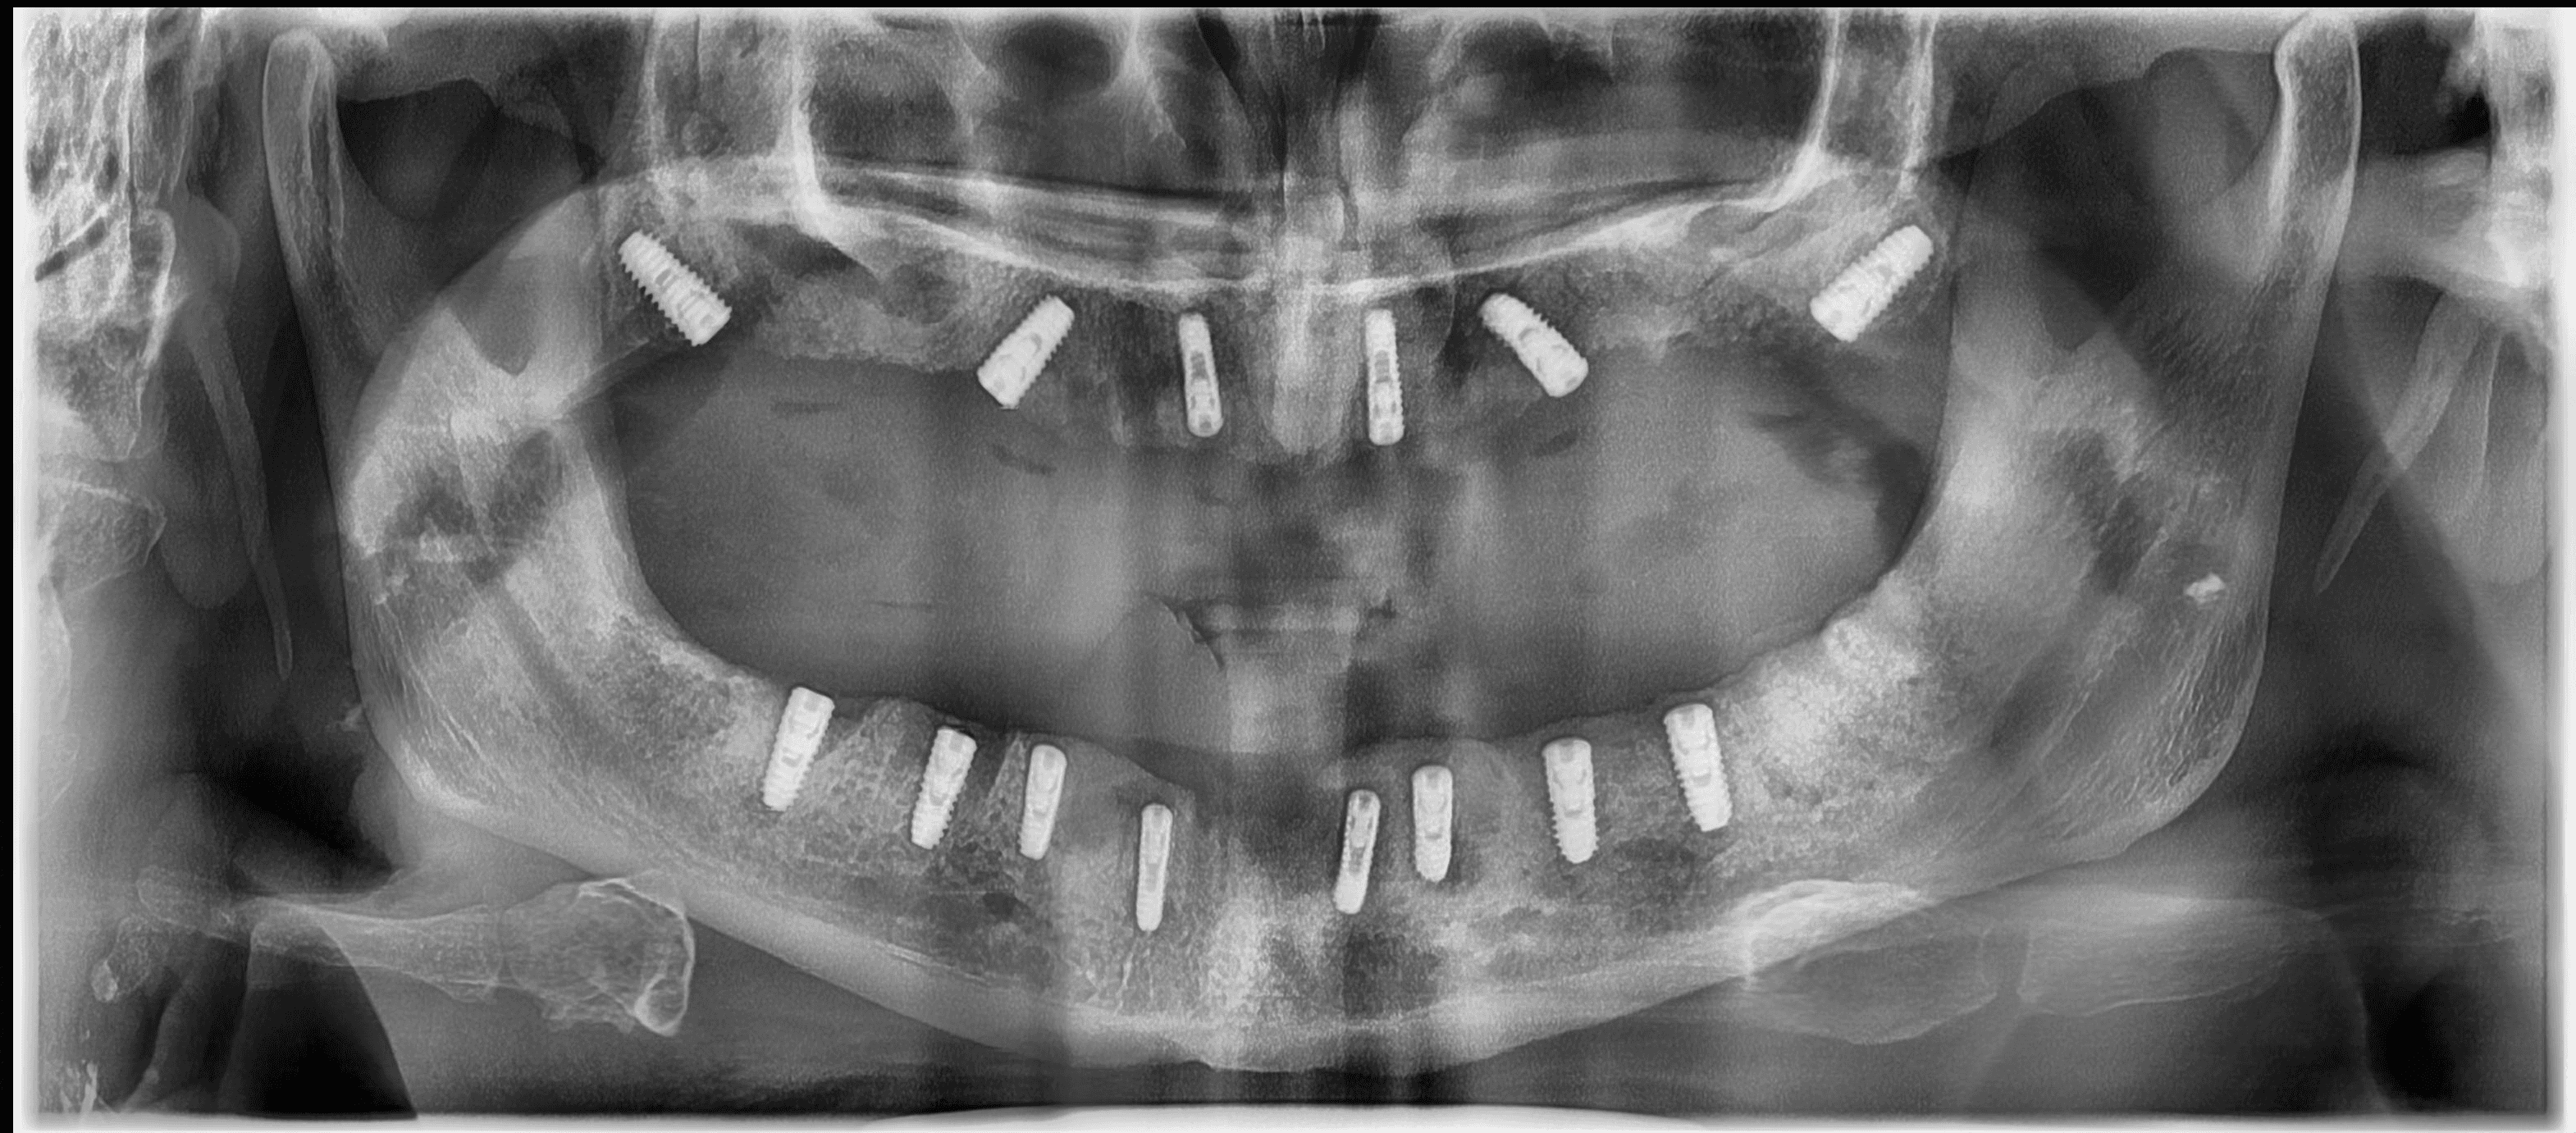

In dental implant cases, CT scans and bone grafting are sometimes required as part of the treatment. We perform a CBCT scan before the procedure to plan the implant precisely, and a post-operative scan to confirm accurate placement. In cases where bone support is insufficient, bone grafting may be needed to improve the long-term success of the implant. All of this is discussed in detail during your planning visit after the initial CBCT scan.

Digital CBCT Planning

3D imaging of your jaw

Helps assess bone quality and volume

Guided Implant Surgery

Implant placement is pre-planned digitally

A surgical guide ensures exact positioning

Case 2: Full Upper Arch Implant (Complex Case)

Patient condition:

Multiple missing and compromised teeth in the upper jaw

Reduced bone support in certain areas

Treatment approach:

Full upper arch rehabilitation

Multiple implants placed with guided surgery

Bone grafting in selected regions

Cost:

₹X,XX,XXX – ₹X,XX,XXX (varies based on implant type and grafting extent)

Outcome:

Restored function (ability to chew properly)

Improved aesthetics and smile

Stable, long-term solution

These cases require:

Detailed planning

Surgical expertise

Precise execution